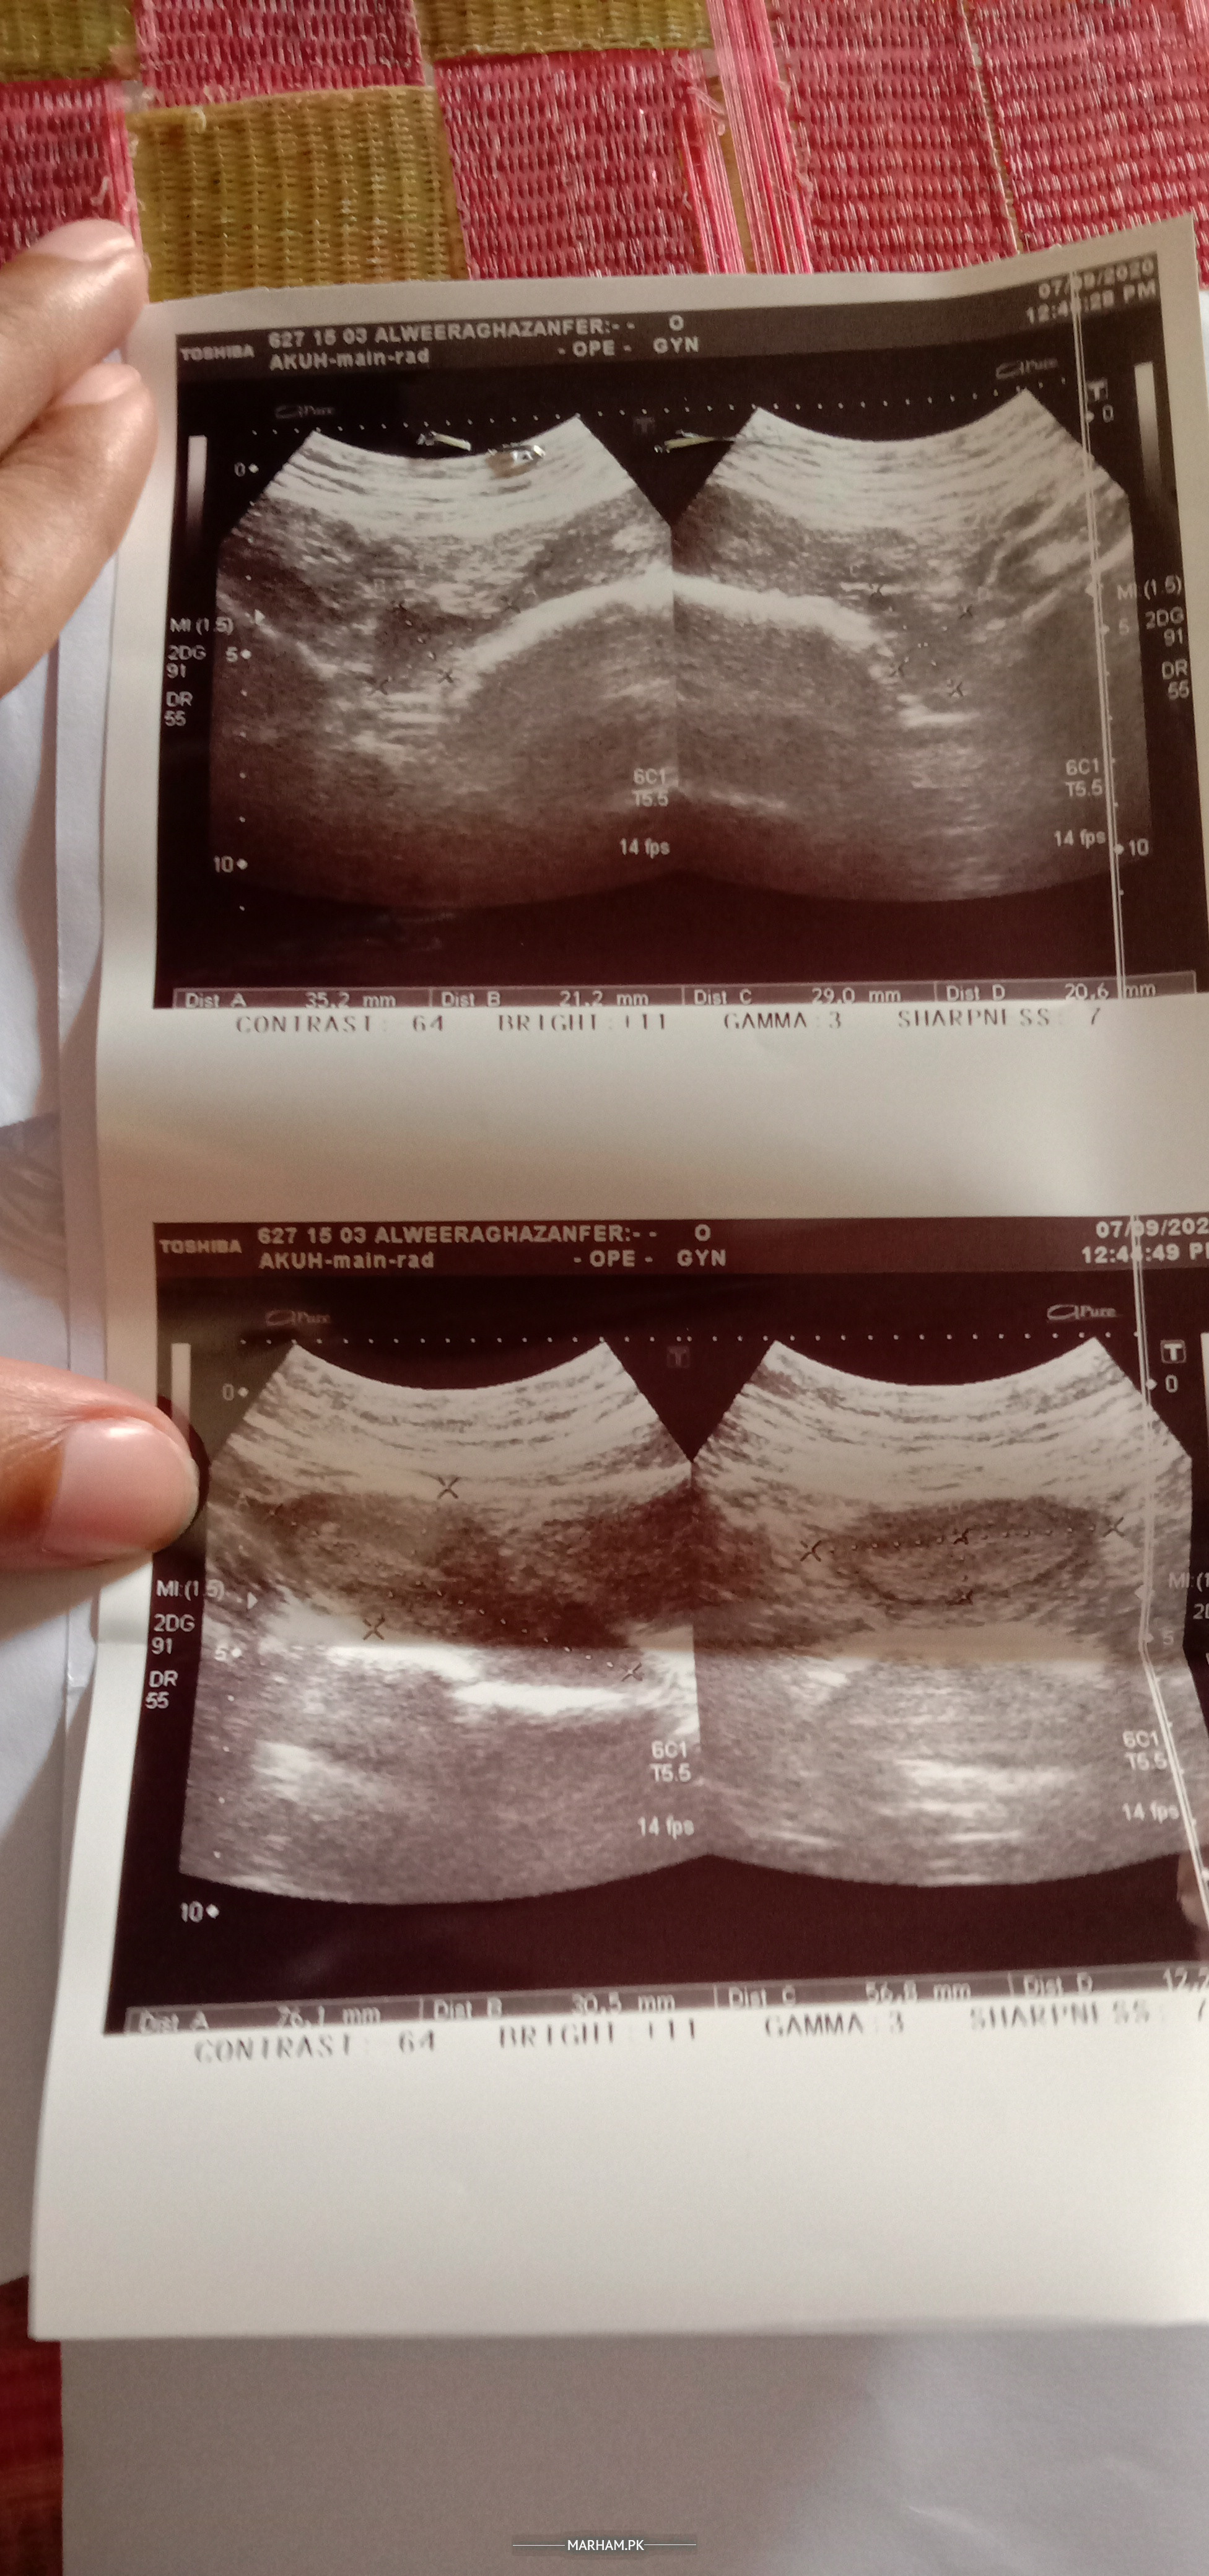

Here is my pelvis ultrasound, please tell me if everything is fine and I don't have PCOS.

plz tell me is everything fine and I don't have PCOS. I have attached my ultrasound report above.